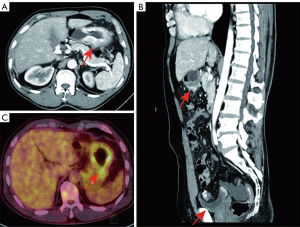

A 62-year-old gentleman was admitted in the Second Affiliated Hospital of Zhejiang University, School of Medicine, with a 20-day history of worsening weakness and poor appetite. This was associated with discomfort of the right flank, hard stools and a loss of weight of 5 kg over one month. No nausea, vomiting or fever were reported. The patient had no history of renal disease. Physical examination on admission revealed BMI of 24.2 (a height of 172 cm and a weight of 71.6 kg). Left cervical lymph nodes were not palpable. Mild tenderness was present in the epigastric region. Gastroscopy showed a huge annular irregular mass on the wall of lower two thirds of the gastric body with peripheral mucosa edema (Figure 1). Biopsy confirmed the presence of a low-grade adenocarcinoma. Abdominal enhanced CT scan revealed a large-scale thickness (size of 9 cm) of the gastric wall with serosa invasion, infiltration of the left lower ureter, multiple enlarged perigastric lymph nodes (lymph nodes No. 2, 4, 5, 6), suspicious metastatic nodes in greater omentum, and a small amount of pelvic effusion (Figure 2). Furthermore, 18F-fluorodeoxyglucose (FDG) PET/CT scan showed that diffuse enhancement in the stomach (SUVmax =6.72), perigastric lymph nodes (SUVmax =4.22), a blurry omentum and a small amount of pelvic effusion (Figure 2).